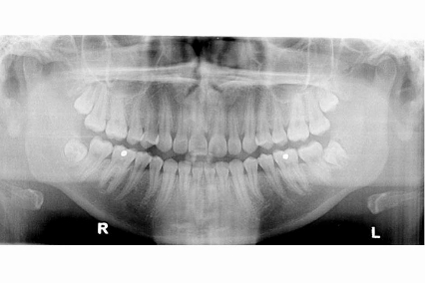

Our team of dentists practice dental and oral surgery from more simple cases to more complex. If necessary, you will be referred to an oral surgeon for more serious cases. We proceed according to clinical and radiological assessments, as well as by the patient’s medical history. Careful attention is given to adjacent tissues and structures.

The extraction of wisdom teeth is one of the procedures that are done regularly. The 3rd molars, commonly called wisdom teeth are often useless for chewing. Due to a lack of space in the mouth, these teeth grow only partially or remain in the gums, which in some patients can cause complications. Your dentist will advise you if surgery is required.